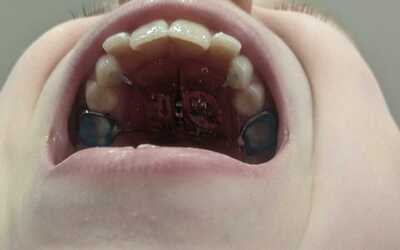

Фото результата упражнений за первый месяц прикладываю:

Дочка также прошла ортодонтическое лечение по расширению верхней и нижней челюсти. Предполагаю, что этого можно было избежать, если бы внимание на вальгус обратили немного раньше.